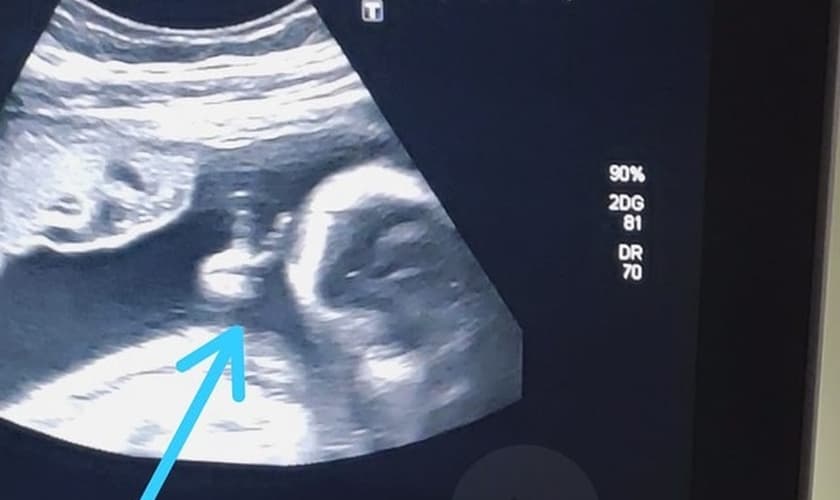

Durante o ultrassom, o bebê surpreendeu a todos ao fazer o sinal de “V de vitória”. “Até a médica falou: 'olha, ele fez o sinalzinho de vitória com a mão'. Eu fiquei sem acreditar”, confessou Felipe.

Segundo o pai, o gesto de seu filho Davi foi um sinal de Deus para ele, dizendo que vai conseguir superar o tratamento e vencer o câncer.

“O filho que eu pedi para Deus foi para superar tudo isso que estou passando. Esse sinal foi para fechar com chave de ouro, para eu ter certeza que vou vencer. Se não tivesse ido, não teria visto isso, porque minha mulher não ia conseguir gravar. Aí, eu vou para o ultrassom e tem um sinal desse, parece que é para a minha fé aumentar. Me dá mais força para poder vencer o câncer. Com certeza, foi um sinal divino”, celebrou.